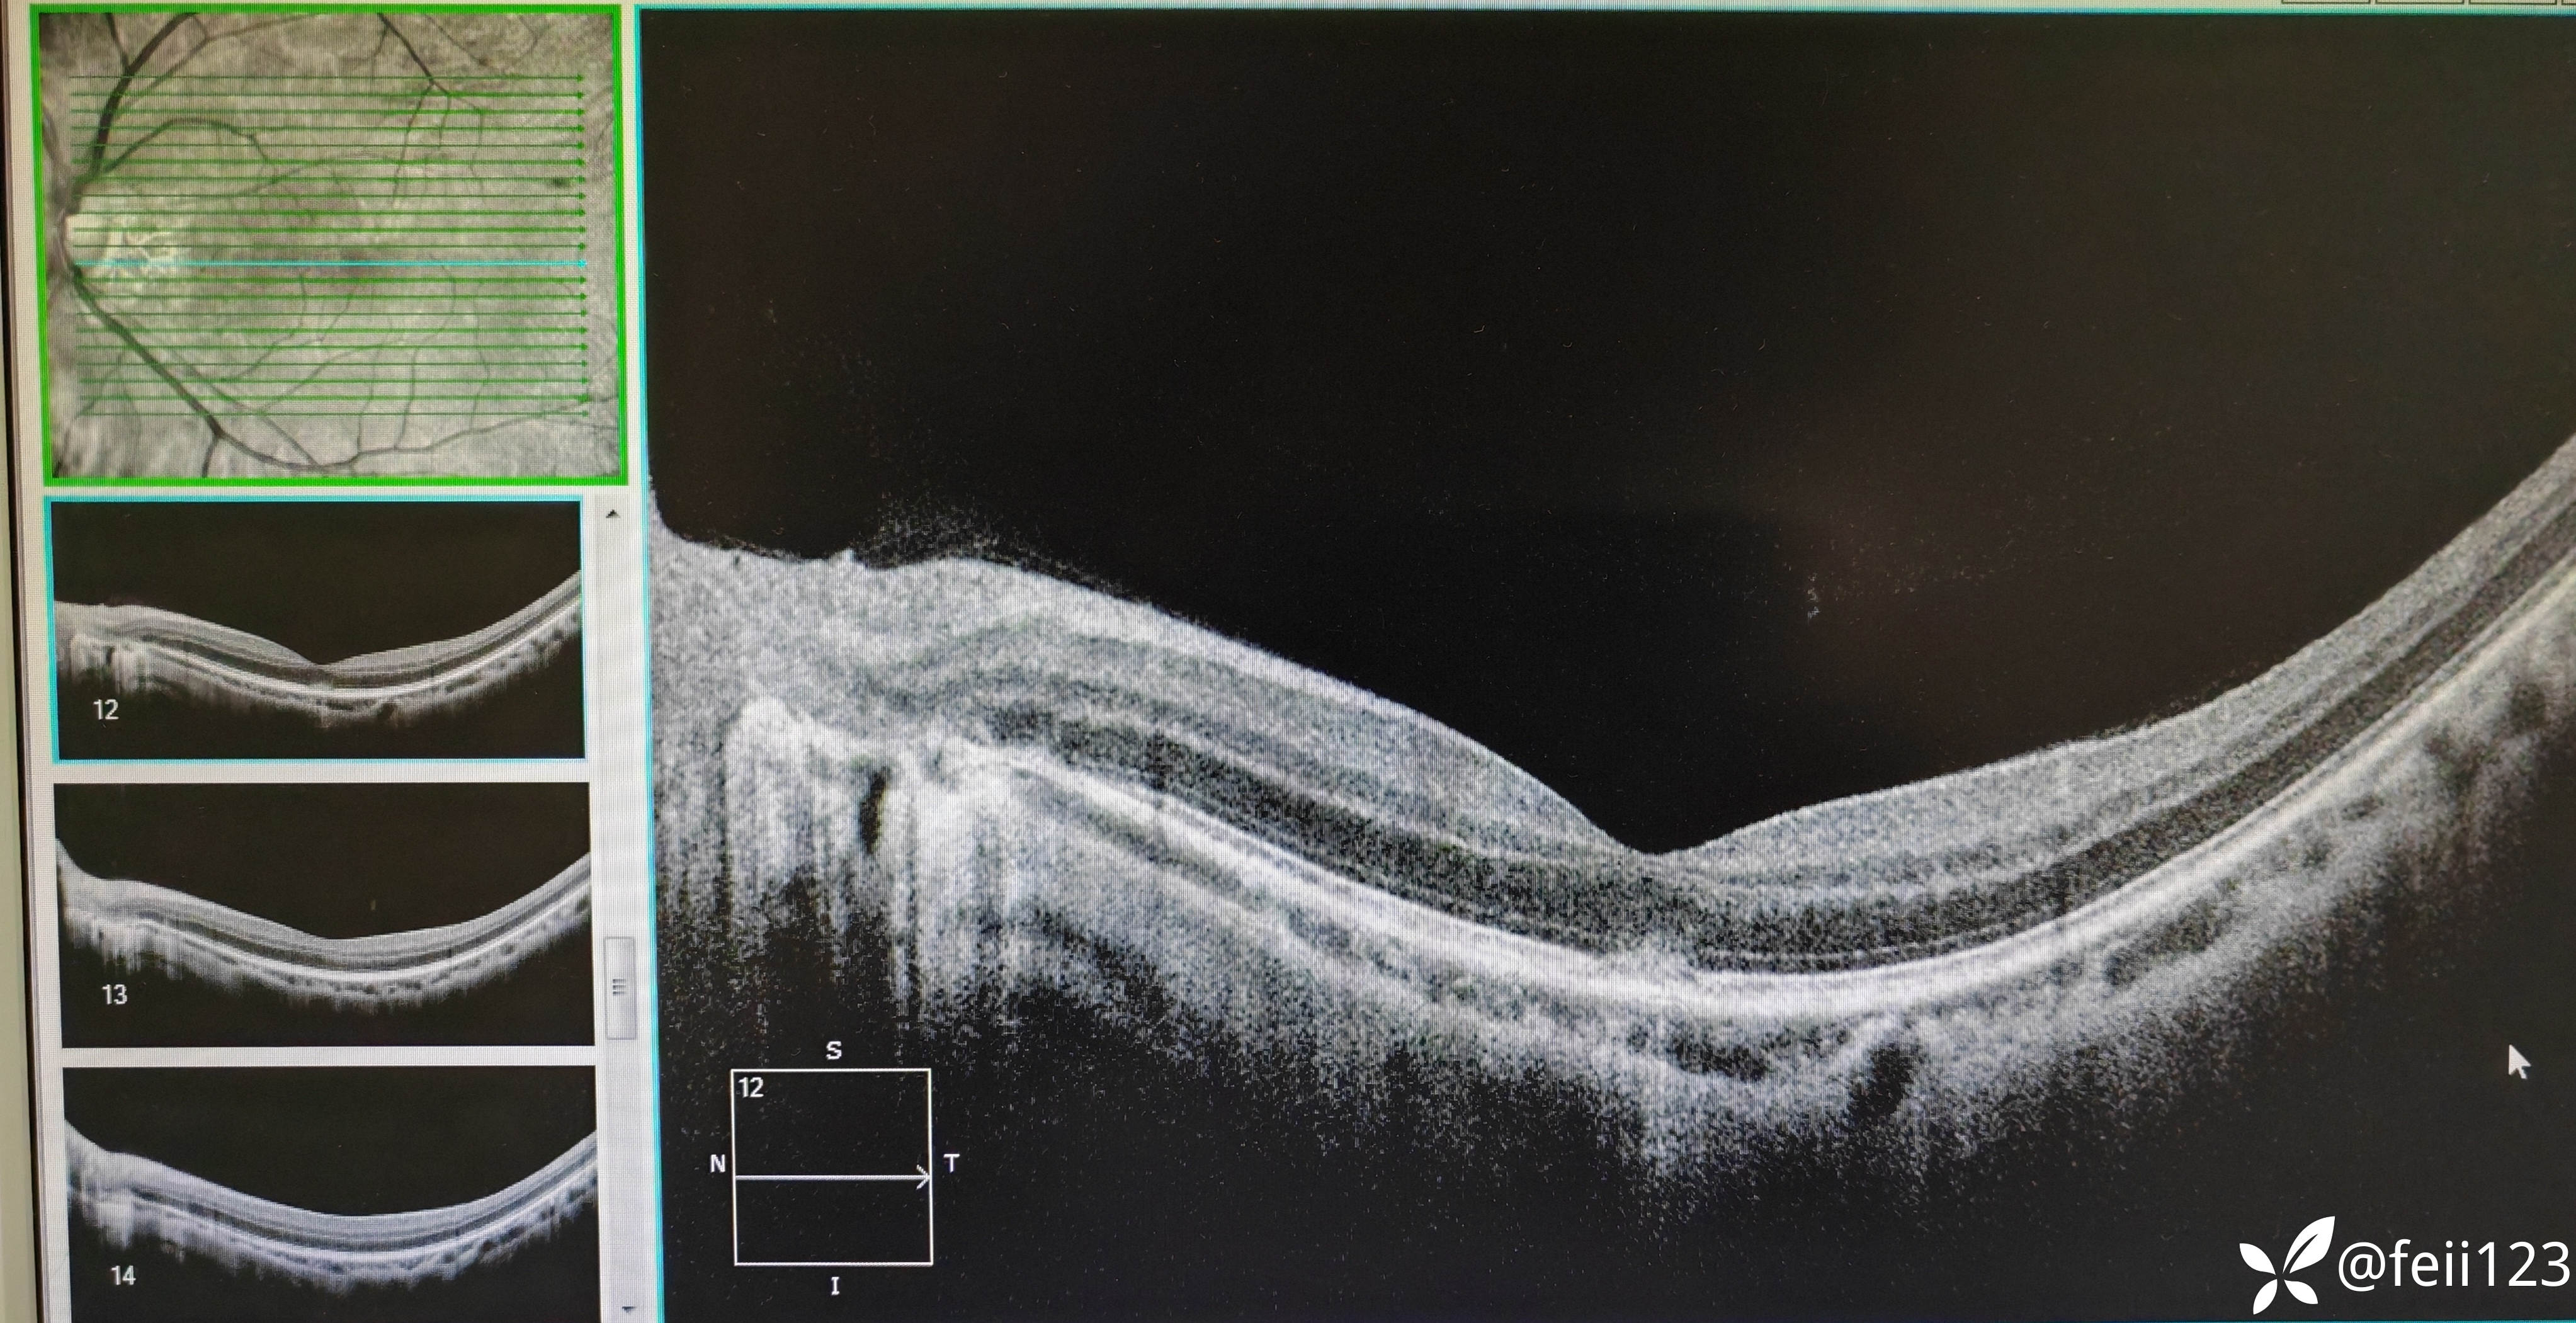

患者信息】:年轻男性30岁

【主诉】:左眼前黑点5天,无诉闪光感

【现病史及既往史】:无特殊,无全身病,中高度近视史

【检查】矫正视力右眼1.0左眼0.4,眼压正常15 16,眼前段未见异常,玻璃体清,眼底如图,左眼底可见后极部及鼻侧周边多个白点。